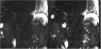

La pancreatitis aguda es una patología común y potencialmente grave que tiene un curso clínico muy variable. Este artículo pretende revisar el papel de las distintas técnicas de imagen en el manejo de esta entidad, describir sus principales manifestaciones radiológicas y la nomenclatura específica asociada a esta entidad.

Acute pancreatitis is common; the clinical course of this potentially severe condition varies widely. This paper aims to review the role of different imaging techniques in the management of acute pancreatitis, describe the main imaging findings for this entity, and explain the terms and criteria used to classify them.